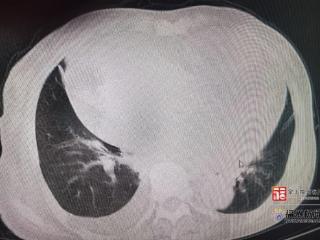

老人不明原因乏力、食欲下降?专家提醒:这可能是无声警报